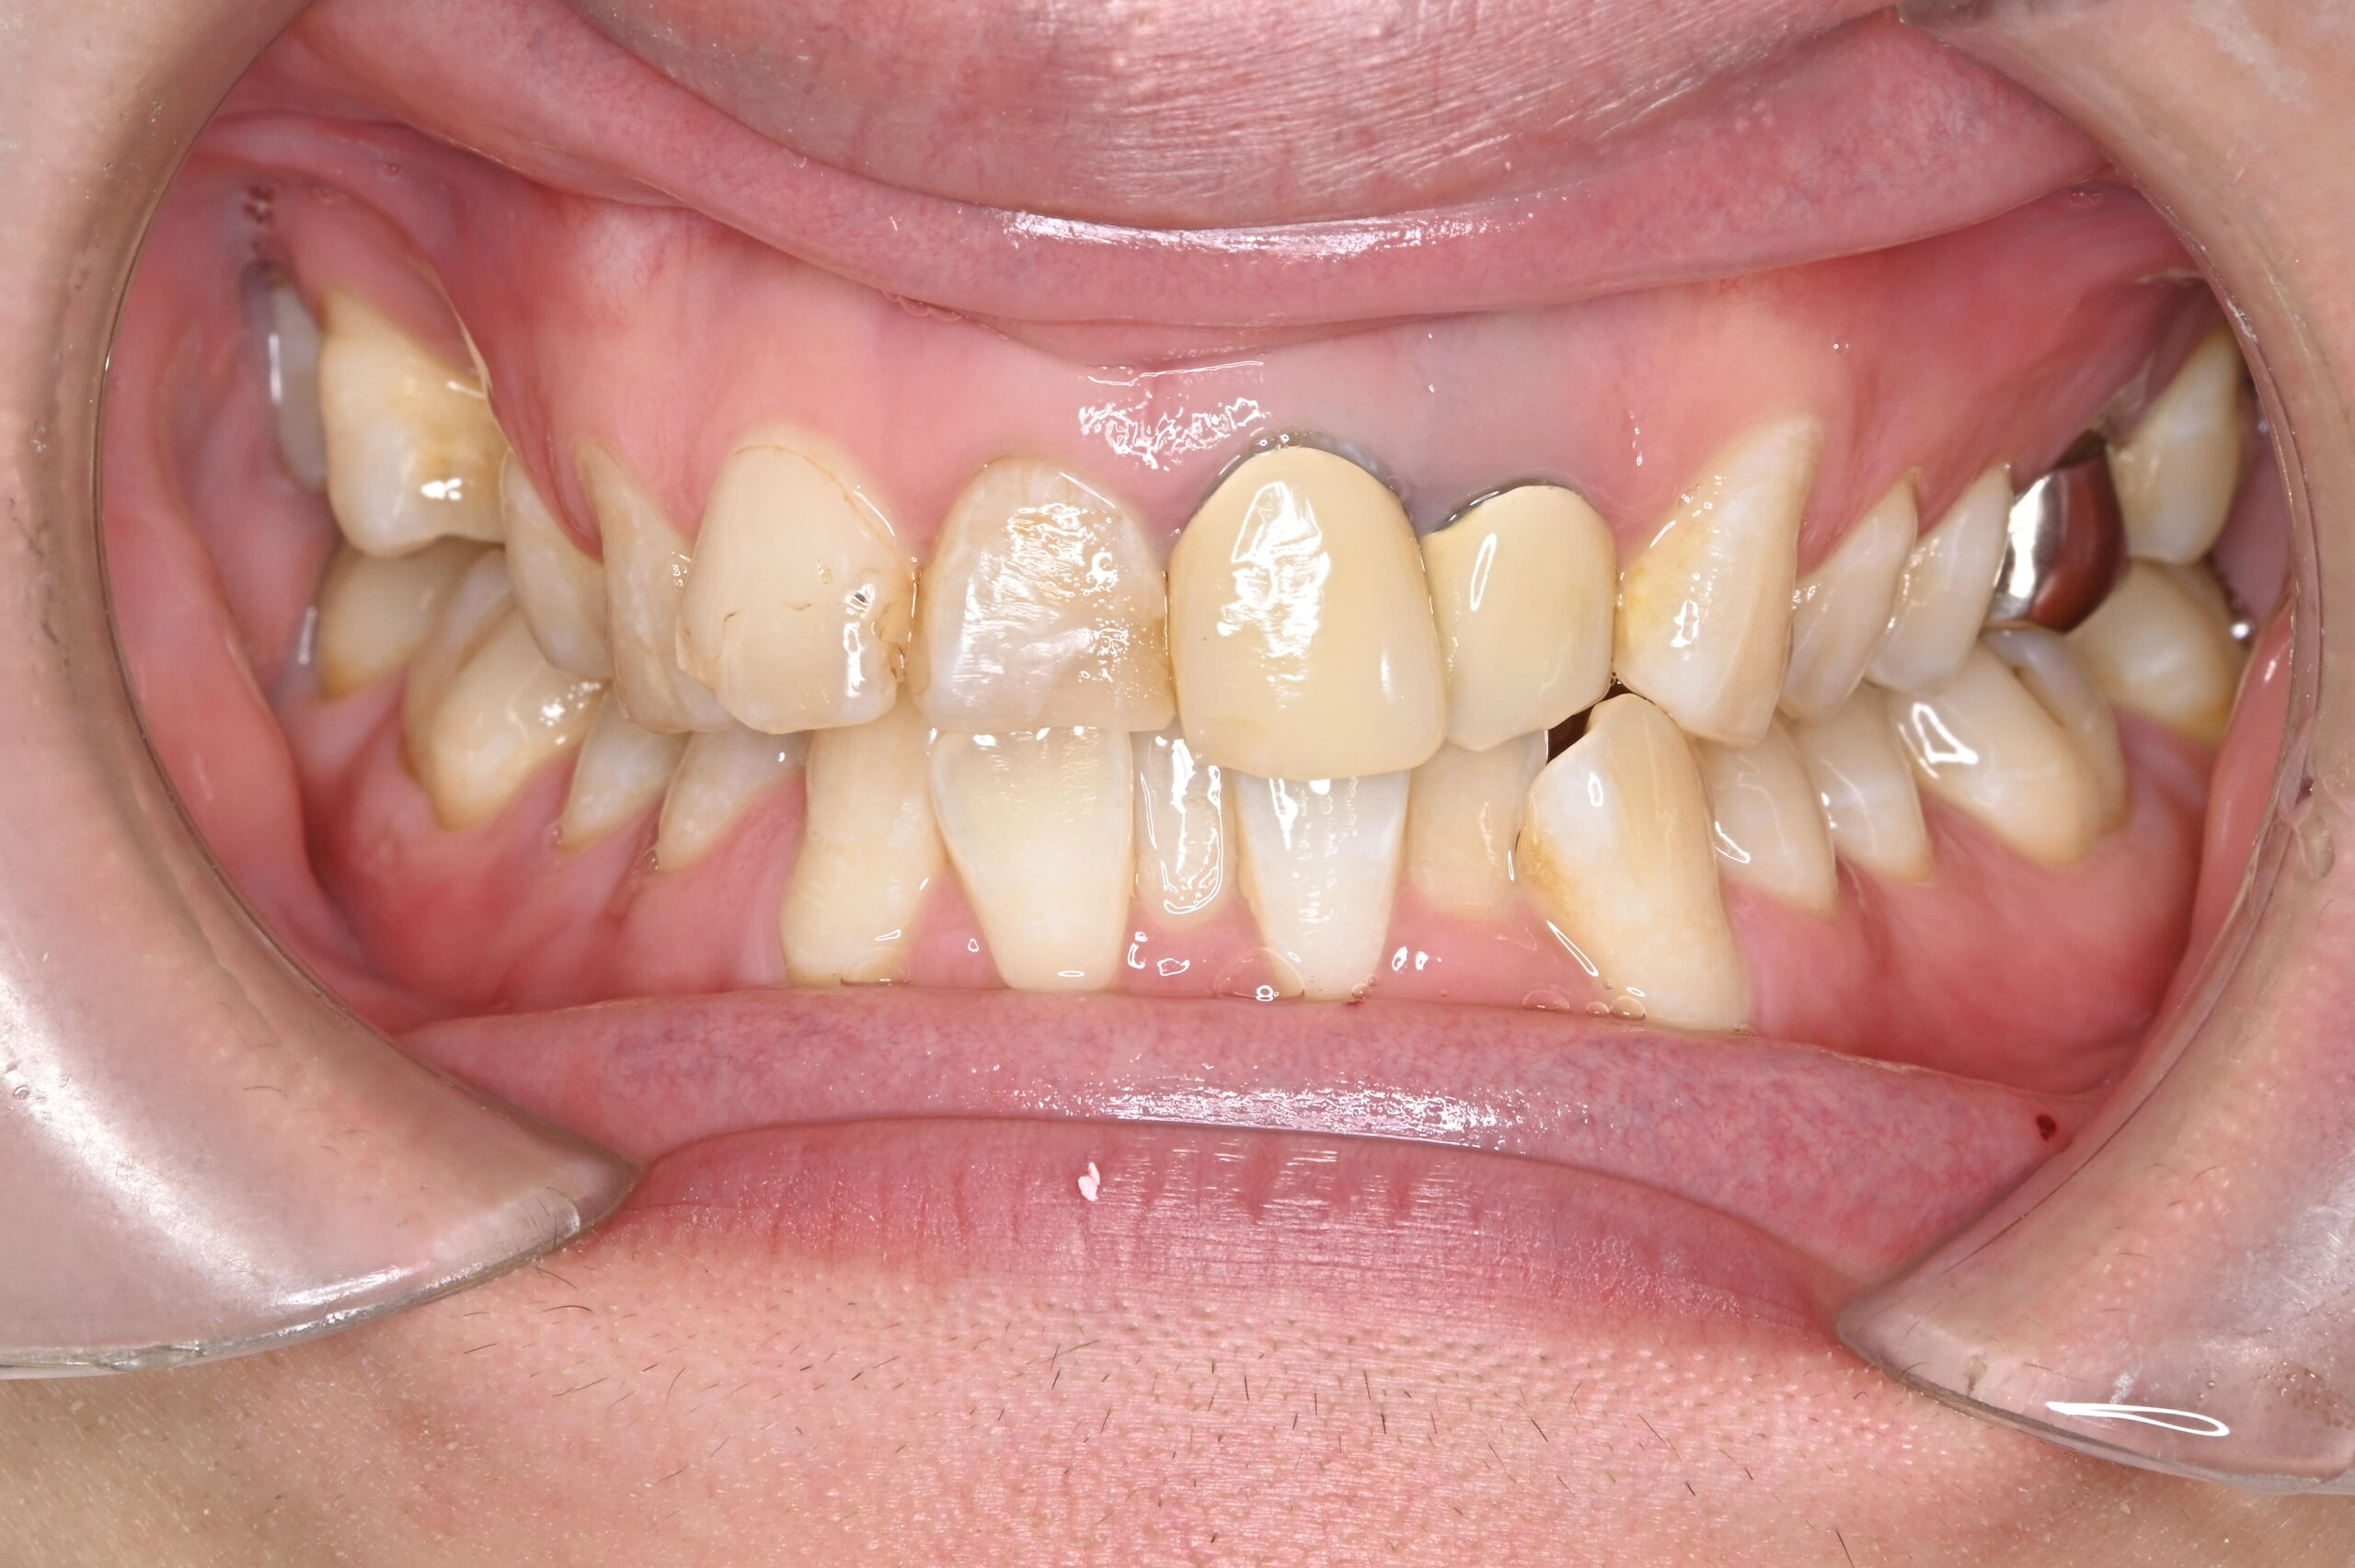

ジルコニアセラミックによる前歯3本の審美治療

年齢・性別

20代/男性

主訴

前装冠のブラックマージンが気になり、HPを見て「ぜひここでジルコニアセラミックにしたい」と来院

治療方法

ジルコニアセラミック(左上1,右上1・2 )

費用

ジルコニアセラミック 110,000円×3本

合計 :330,000円

*価格は税込です

メリット

• ブラックマージンの心配がない

• 自然なツヤと色合いがずっと保たれる

デメリット・

副作用

• 特にセラミック部分に欠ける可能性がある

• 高価である